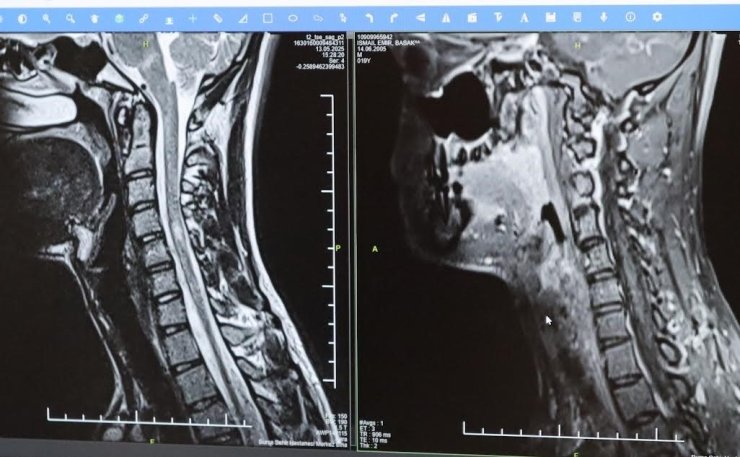

Bursa Şehir Hastanesinde görevli Nöroloji Uzmanı Prof. Dr. Özden Kamışlı, 30 Mayıs Dünya MS Günü kapsamında açıklamalarda bulundu. MS'in, bağışıklık sisteminin sinir sistemine saldırmasıyla gelişen kronik bir hastalık olduğunun bilgisini veren Prof. Dr. Kamışlı, "Dünyada yaklaşık 2.8 milyon MS hastası olduğu bilinmektedir. MS genellikle 20-40 yaş arası gençleri etkilemektedir. Bununla birlikte çocukluk döneminde ya da ileri yaşta da ortaya çıkabilmektedir. Kadınlarda görünme sıklığı erkeklere göre bir buçuk kat daha fazladır" dedi.

MS hastalarının çeşitli şikâyetlerle hekimlere başvurduğunu vurgulayan Kamışlı, "Bunlar arasında görme bozukluğu, kol ve bacakta kuvvetsizlik, uyuşmalar, dengesizlik, yürüme bozukluğu, idrar problemleri veya aşırı yorgunluk ve halsizlik hali bulunmaktadır. MS ataklarla seyredebilir ve genellikle en sık görülen formu budur. Birdenbire bir şikâyet ortaya çıkar ve zamanla azalır veya kaybolur. Bir de progresif dediğimiz ilerleyici formu vardır. Bu ilerleyici formda hastalık yavaş yavaş ilerlemektedir. MS her hastada farklı seyreder. Bu nedenle tek tip bir MS hastalığından bahsetmek mümkün değil" şeklinde konuştu.

Hastalığın tanısını ne kadar erken konulursa ve tedaviye ne erken başlanırsa; hastaların günlük hayatta aktif ve üretken bir şekilde devam etmelerinin o kadar kolaylaştığına dikkat çeken Kamışlı, "Günümüzde MS'le ilgili çok fazla gelişme oldu ve tedavi seçenekleri arttı. MS merkezlerinde bu tedavi seçeneklerine ulaşmaları mümkün. Hastalarımız için doğru tanı, düzenli takip ve uygun tedavi oldukça önem teşkil etmektedir" diye konuştu.